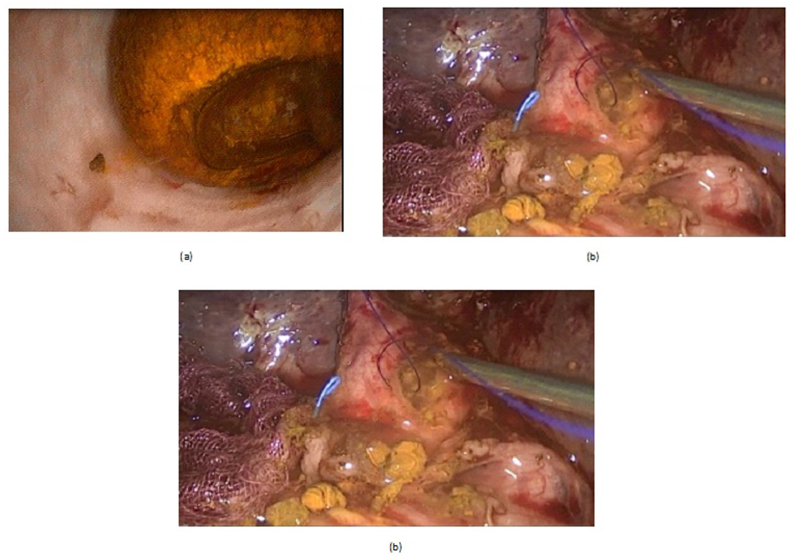

LCD: Under general anesthesia; we used the standard four-port technique of LC. Routine trans-cystic intra-operative cholangiography (IOC) was performed in all cases for identification of stones number, site and size. The gallbladder was left in situ for retraction until the operation was completed. When we reached CBD, a longitudinal supraduodenal choledochotomy(1.5–2 cm) was done using scissors or cautery. The CBD stones were entirely retrieved in all patients using cholecodoscopic extraction techniques (4.5-Fr flexible choledochoscope; Karl Storz, Tuttlingen, Germany) by irrigation, balloon or basket with mechanical lithotripsy when needed. The epigastric port was used to accommodate the operating choledochoscope [ref. 15,ref. 18,ref. [26], ref. [27], ref. [28], ref. [29]]. After all stones were retrieved and clearance of the bile duct was confirmed with choledochoscopy, the choledochotomy was closed with interrupted 4.0 Vicryl sutures in patients with primary closure of CBD and then IOC was done through the cystic duct to confirm absence of stones and leak (Fig. 1). On the other hand, for patients with T-tube drainage, the T-tube was placed in the choledochotomy and secured with sutures, Patients had a cholangiogram on the 6th postoperative day. If the finding was normal, the T-tube was clamped and patients were discharged home with the T-tube in situ then it was removed from 4 to 6 weeks later after normal tube cholangiogram in the outpatient clinic. [ref. 23,ref. 27,ref. 30]. Lastly, laparoscopic HJ was done by 4.0 polydioxanone (PDS) sutures (posterior and anterior interrupted sutures) and a tube drain was placed near the anastomosis and removed days after the operation (Fig. 2) [ref. 1,ref. 14,ref. 31,ref. 32].

OCD: It started by open cholecystectomy (OC) and IOC through the cystic duct; then identification of CBD and the junction between the cystic duct and the CBD were done. A complete Kocher’s maneuver was performed in order to feel the retro- and intra-pancreatic portion of the CBD for easy extraction of stones and to feel the papilla. Then, two stay sutures were placed transversally at the right and left portions of the duct; then the anterior wall of the supraduodenal part of CBD was opened. The incision was performed with a sharp scalpel, then an exploration of the CBD first proximally and then distally with the Randall forceps occurred for extraction of visible stones. The proximal and distal CBD was then irrigated with saline using a soft catheter. In choledochoscopic cases, the CBD stones were entirely retrieved using choledochoscopic extraction techniques (4.5-Fr flexible choledochoscope; Karl Storz, Tuttlingen, Germany) (Fig. 5, Fig. 6). After all stones were extracted and clearance of the bile duct was confirmed; the management was as mentioned in LCD (Fig. 3, Fig. 4). Lastly, in HJ cases, the biliary-enteric anastomosis was done by 4.0 PDS sutures (posterior continuous and anterior interrupted sutures) [ref. 20].